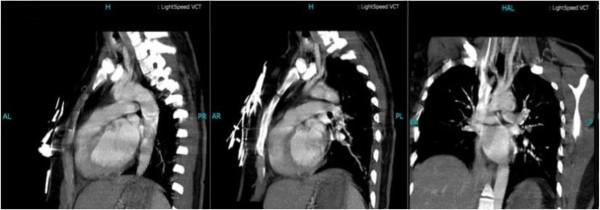

A 35-year-old Chinese woman presented to the Emergency Department with left hemiparesis, pain and numbness of her arms and weak radial pulses. Her laboratory results showed an elevated C-reactive protein and erythrocyte sedimentation rate, and subsequent digital subtraction angiography demonstrated narrowing and occlusion of the major branches of her aortic arch. We report the case of a patient with Takayasu arteritis presenting with a massive cerebral ischemic infarct and review the current literature on this topic.

一名35岁的中国女性因左侧偏瘫、手臂疼痛和麻木以及桡动脉搏动减弱就诊于急诊科。她的实验室检查结果显示C反应蛋白和红细胞沉降率升高,随后的数字减影血管造影显示其主动脉弓主要分支狭窄和闭塞。我们报告一例患有高安动脉炎并出现大面积脑缺血梗死的患者病例,并回顾关于该主题的当前文献。